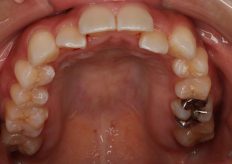

Before

| 症状 | 上下顎前歯部叢生 |

| 治療内容 | インビザライン アライナー矯正 |

| 治療期間 | 8ヶ月 22枚 |

両脇上の前歯が内側に入っているのを治したいとのことで来院されました。

上の前歯が後ろに引っ込んでいるせいで下の前歯もデコボコになってしまっています

前歯の位置が今より前に出ないように前歯6本歯と歯の間を少しずつ削り(IPR)矯正を行いました。

アライナーを指定の1日20時間の装着2週間毎の交換を行い綺麗な歯列になりました。